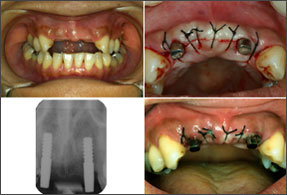

| 1ピースでの審美性の工夫(1) | |

| 植立直後の暫間被覆冠装着とその後のブラッシング | |

![]() ?上顎前歯2~2欠損の右上2,左上2に4LMを植立。植立直後にアルジネート印象を採り、翌日洗浄時までにTekを準備する。 |

![]() ?抜糸の2~3日後から術後用スーパーソフトブラシでブラッシングを再開、術後3~4週後には通常のブラシに戻って磨いてもらう。ブラッシングにより暫間被覆冠周囲の粘膜を十分引き締め、術後2ヵ月後に形成印象を行う。印象後はTek内外面に即重レジンを盛り、最終Crに近いTekの作成を心がける。 |

| 植立3Y後 | 最終TEKとBr装着 |

![]() ?Br装着。2004/08/30 |

![]() Br装着時の審美性を保っている。2007/05/09 |